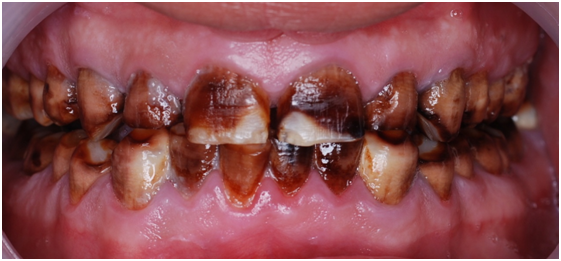

Figure 2 Pre op front view.

A 22 Yemeni male patient presented to the College of Dentistry clinics at the University of Dammam seeking cosmetic treatment with a chief complaint “I want to improve the way my teeth look " He reported no significant medical history. Patient has never been into the dental clinic. He stated his deciduas teeth were normal and his whole village complains of darkened teeth (brownish). A panoramic x-ray (Figure 1), intraoral pictures (Figures 2−6) as well as study casts were taken to diagnose the case (Figure 7). Upon examination, the patient was found to suffer from severely generalized discoloration of permanent teeth and moderate dental attrition resulting in shortening of the vertical dimension of occlusion (VDO). A class I occlusion with class I canine relation was present, with an over-bite of 4mm and an overjet of 4mm. The upper lip seems stretched with dropping mouth angles. The patient suffers from generalized marginal chronic gingivitis with no mobility or furcation involvement noticed. The treatment plan started with plaque control measures were conducted as well as patient education. The patient's esthetic problem caused by Fluorosis both teeth staining and facial appearance and occlusion. The treatment options available range from bleaching, porcelain veneers, full coverage ceramic crowns or porcelain fused to metal crowns. Due to the Fluorosis severity, the bond strength of the adhesive agent was questionable that eliminated the veneers option. Bleaching when tried had minimal effects. Finally, porcelain-fused to metal (PFM) crowns were selected to restore esthetics of anterior teeth, while posterior gold crowns were chosen to raise the occlusion posterior by 2mm. Treatment options were discussed with the patient who consents to the treatment plan.